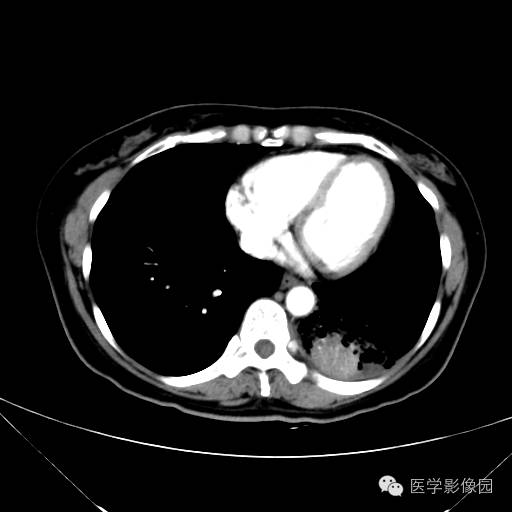

肺叶实变性支气管肺泡癌1例CT影像表现